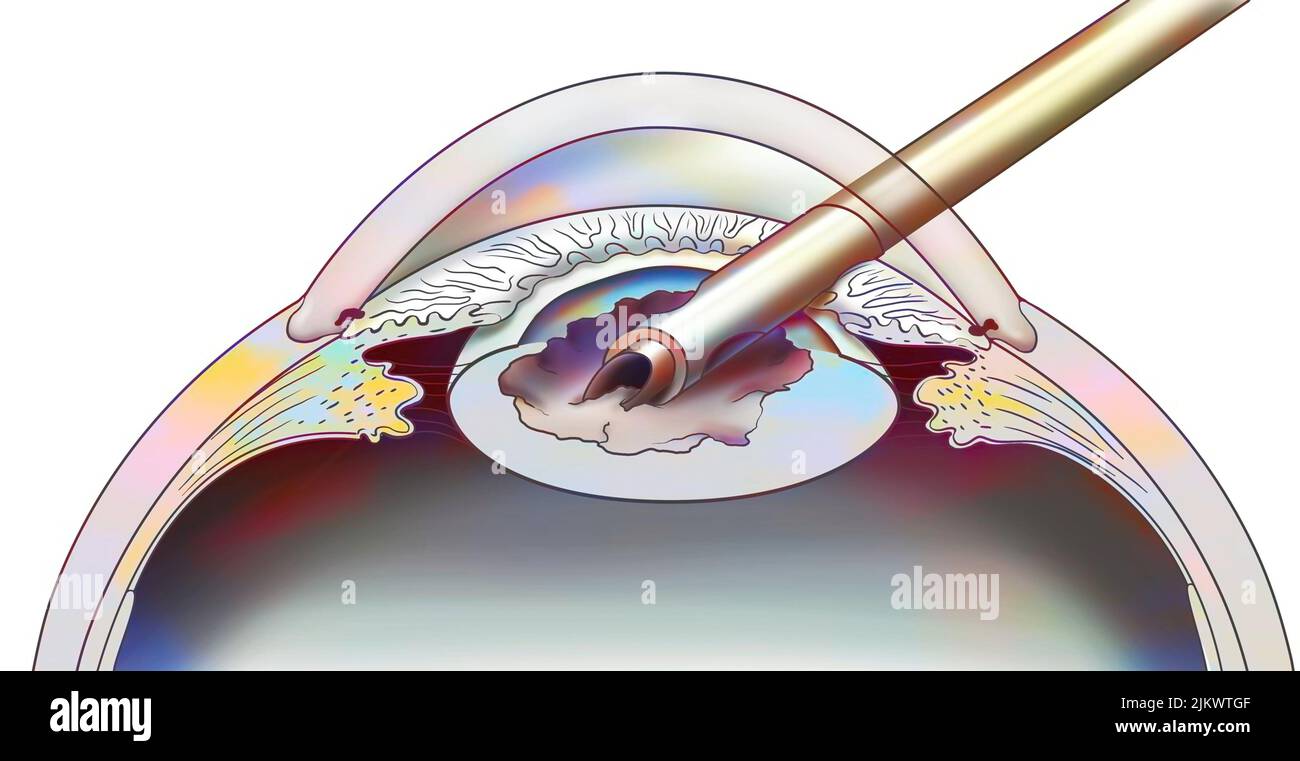

RF2JKWT9A–Oeil, cataracte, phacoémulsification - étape 2: Consiste à casser la lentille avec une sonde.